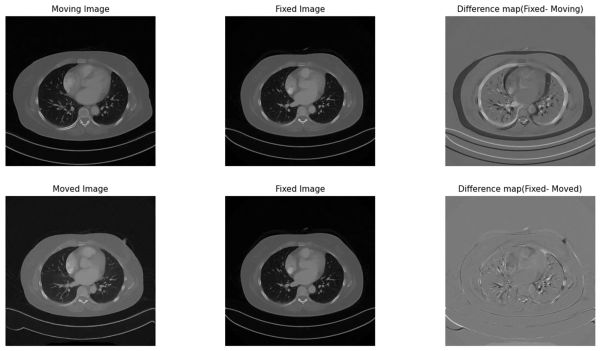

폐암 진단 및 추적을 위한 자동화 RECIST 기술 with Multi-Time Point Segmentation

포스트 코로나 이후 최근까지 폐 건강에 대한 관심이 크게 증가하고 있습니다. 이러한 현상은 폐암, 만성 폐쇄성 폐 질환(COPD), 천식, 폐 섬유증과 같은 폐 관련 질환의 증가와 밀접하게 관련되어 있습니다. 폐 질환의 증가는 전 세계적으로 수많은 사망 원인과 장기적인 건강 문제를 발생시키고 있습니다. 이에 따라 폐 건강에 대한 연구와 치료